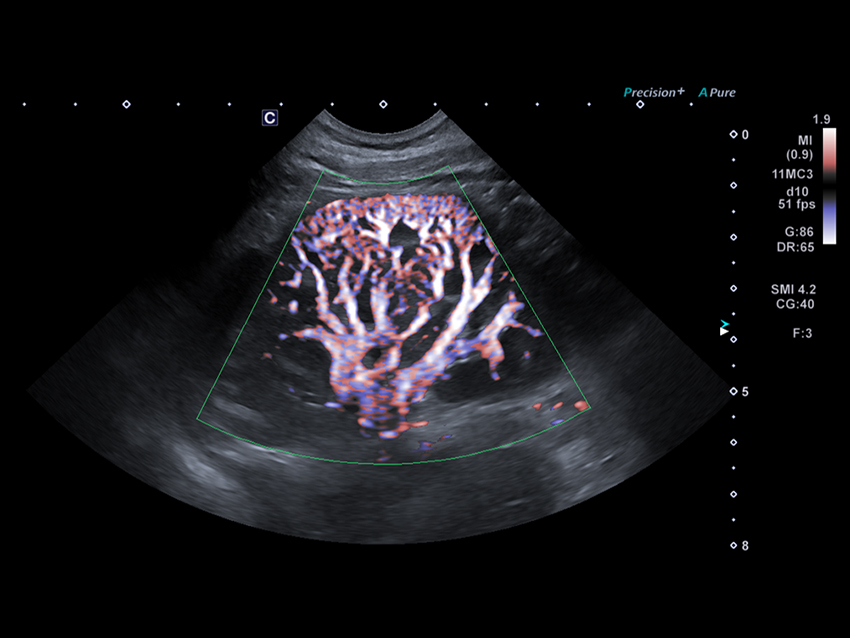

Технологія візуалізації мікропотоків (SMI) відображає кровотоки низької швидкості у нирці.

Висока частота кадрів підтримується за допомогою SMI відображаючи перфузію в нирці при використанні мікроконвексного датчика.